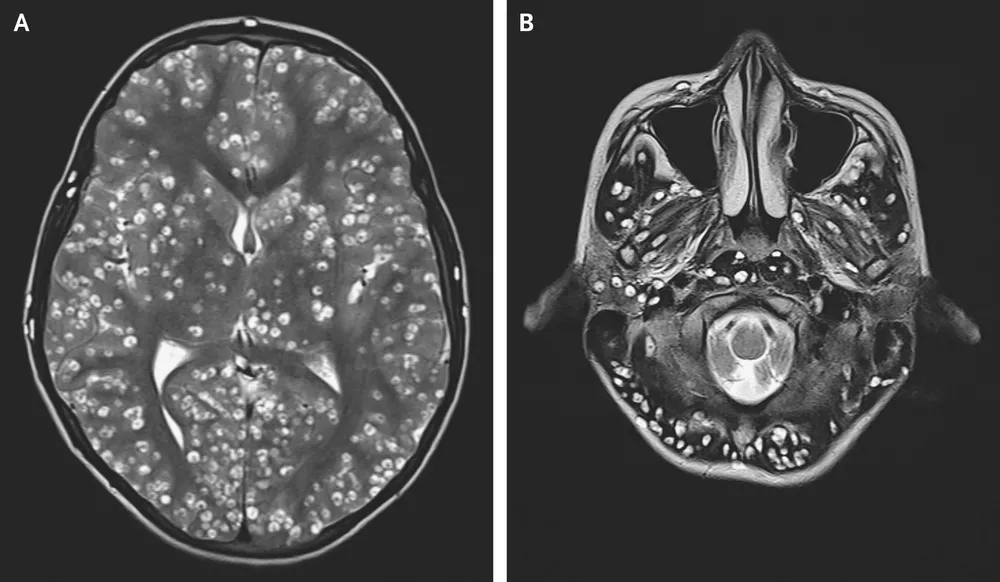

No caso tratado no estudo, o problema só foi identificado depois que os médicos realizaram uma ressonância magnética e viram os danos causados pelos cistos no córtex e no tronco cerebral do paciente, incluindo o cerebelo, que fica na parte de trás do cérebro, acima da medula espinhal.

Exame mostra os nódulos causados por ovos de parasitas em cérebro de jovem indiano — Foto: ESIC Medical College/Divulgação